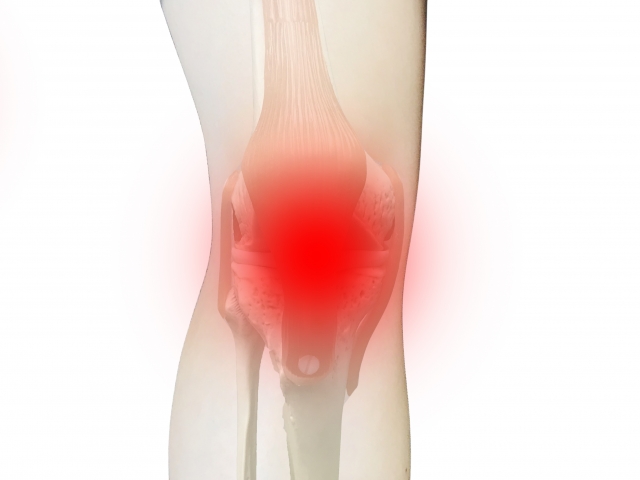

ジャンパー膝は膝蓋腱炎と言われ膝の皿についている腱が炎症を起こして痛みがでる症状です。

痛みによって思いっきり飛んだり、走ったり、しゃがんだりができなくなるのが特徴です。炎症症状なので安静にしていて早く改善することもありますが、なかなか炎症が収まらずに症状が長引く場合もあります。

膝の過度な屈伸運動により周囲の腱や膝を伸ばす大腿四頭筋に負荷がかかり炎症が起こる事により発症します。このため使いすぎ症候群とも呼ばれています。また柔軟性も関係しており、成長期に骨の成長に筋肉の成長がついていけずに緊張が増すと言う場合もあります。

膝蓋腱とは膝のお皿の少し下あたりに位置していて膝立ちしたときに当たる所になります。好発部位は皿の下から膝蓋腱の付着部が7割、皿の上の四頭筋付着部が2割、膝蓋腱の中央から脛の付着部にかけてが1割と言われています。

◎ 膝を伸ばして座った状態でお皿の下を押して痛めばジャンパー膝の可能性があります。